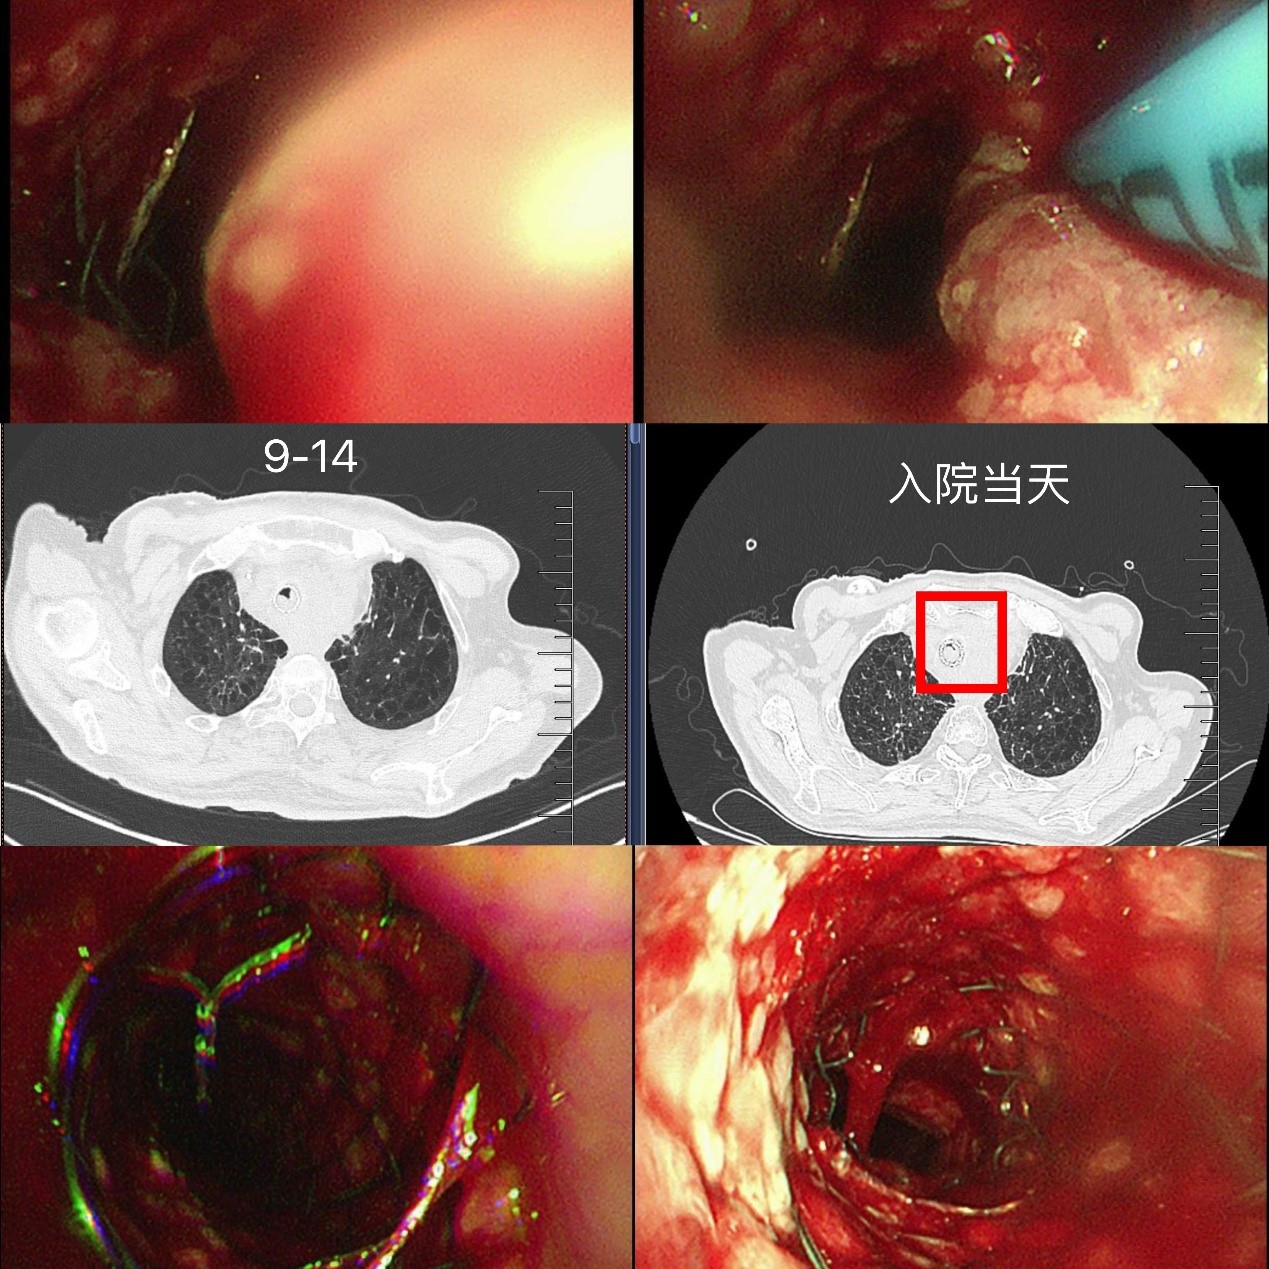

迅速排除手术禁忌,蒋军红主任团队为龚先生实施“支气管镜下主支气管支架置入术”。术中可见声门下4cm处气管呈混合性狭窄,狭窄长度约2cm,团队精准定位后,成功置入一枚16×40mm金属裸支架。术后2天复查气管镜,支架贴壁良好,仅少量肿瘤从网眼生长,经APC消融治疗。龚先生的胸闷、气喘明显缓解,顺利出院继续后续肿瘤治疗。

出院后,龚先生在苏大附四院肿瘤科接受了放疗(食管肿瘤灶及转移淋巴结)、替雷利珠单抗免疫治疗联合替吉奥口服化疗,8月复查时虽提示纵隔占位增大、局部压迫食管气管,但整体状态尚可。然而,9月中旬,他再次突发胸闷气喘,此时的龚先生虽神志清楚但精神极差,饮食睡眠受严重影响,不能平卧。龚先生被紧急送至我院急诊,收住入院,患者在无创呼吸机辅助下仍呼吸急促、呼吸窘迫。蒋军红主任团队为其紧急手术治疗,在手术室气管镜镜下景象触目惊心:原支架上端新生物已几乎完全阻塞气道,狭窄程度接近95%,且伴有活动后出血,随时可能因血块堵塞或缺氧危及生命。

蒋军红主任团队冷静制定策略:使用APC(氩等离子凝固术)对新生物进行局部消融,减少阻塞,稀释肾上腺素、冰盐水止血,随后快速的在原有支架腔内最狭窄部位,精准叠加置入一枚12×30mm金属裸支架。操作过程顺利,术后支架通畅度显著提升,远端管腔无明显狭窄,同步留取灌洗液送检明确感染与肿瘤情况。